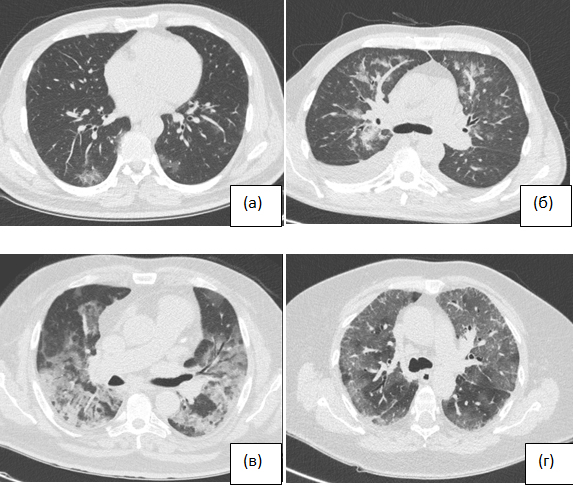

MosMedData: data set of 1110 chest CT scans performed during the COVID-19 epidemic

With the ongoing COVID-19 pandemic decreasing availability of polymerase chain reaction with reverse transcription and the snowballing growth of medical imaging, especially the number of chest computed tomography (CT) scans being performed, methods to augment and automate the image analysis, increasing productivity and minimizing human error are of particular importance. The creation of high-quality datasets is essential for the development and validation of artificial intelligence algorithms. Such technologies have sufficient accuracy in diagnosing COVID-19 in medical imaging. The presented large-scale dataset contains anonymized human CT scans with COVID-19 features as well as normal studies. Some studies were tagged by radiologists using binary pixel masks of regions of interest (e.g., characteristic areas of consolidation and ground-glass opacities). CT data were acquired between March 1, 2020, and April 25, 2020, and provided by municipal hospitals in Moscow, Russia. The presented dataset is licensed under Creative Commons Attribution-NonCommercial-NoDerivs 3.0 Unported (CC BY-NC-ND 3.0).